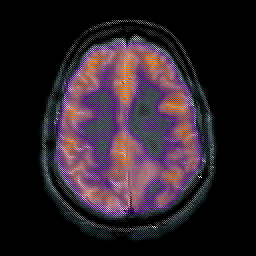

Glioma overlay -- Slice #20

[Home][Help][Clinical] Slice 20